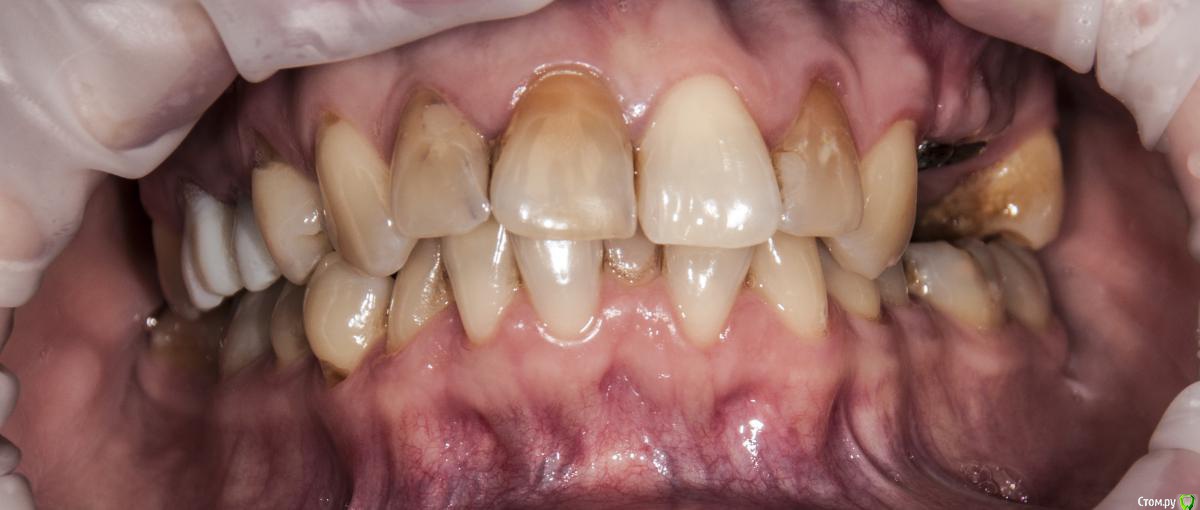

kamranchick Опубликовано 4 мая, 2018 Поделиться Опубликовано 4 мая, 2018 Добрый день Уважаемые коллеги, имеются проблемы с ортодонтией в нашем славном городе.Какие будут предложения по кейсу, сколько визитов и по ценникам, можно в личку.Пациент готов ездить в другие городаP.S пациент тоже будет следить за ходом этой ветки))) Ссылка на комментарий

krokomot Опубликовано 4 мая, 2018 Поделиться Опубликовано 4 мая, 2018 а снижение высоты есть? Ссылка на комментарий

kamranchick Опубликовано 4 мая, 2018 Автор Поделиться Опубликовано 4 мая, 2018 а снижение высоты есть?Ну углы рта опущены, модели не видел Ссылка на комментарий

krokomot Опубликовано 4 мая, 2018 Поделиться Опубликовано 4 мая, 2018 в данной ситуации конечно шляпа у пациента, если совсем все плохо, можно бы, ло бы просанировать для начала, снять скан, затем, поробовать на инвизилайнерах решить основные проблемы в окклюзии , затем тотальное протезирование. Идейка конечно не айс, но всё же выход. Ссылка на комментарий